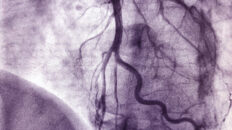

Steht gleich ein ganzes Ärzte- und Pflegeteam bereit, muss direkt behandelt werden. Dann heißt die Diagnose oft „Herzinfarkt“ oder „Schlaganfall“ und der Patient wird im sogenannten Schockraum versorgt, dem Herz einer jeden Notaufnahme. Hier steht alles bereit, was Menschenleben retten hilft: Defibrillator, Beatmungsgerät, Monitoring, Perfusoren, EKG, Medikamente und vieles mehr. Der Hightech-Raum ermöglicht lebensrettende Untersuchungen und Behandlungen, ohne dass der Patient in einen anderen Trakt der Klinik gebracht werden muss. Das spart wertvolle Zeit.